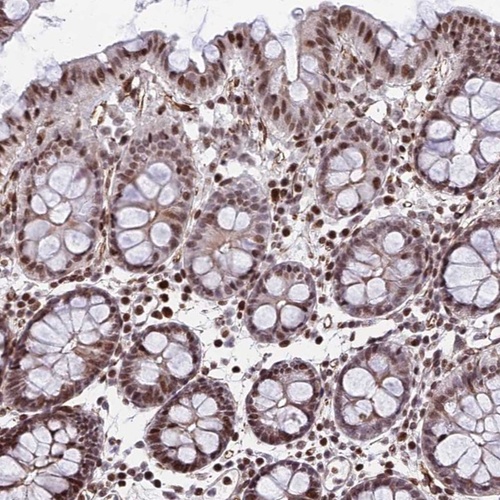

Immunohistochemical staining of human colon shows strong nuclear positivity in glandular cells.